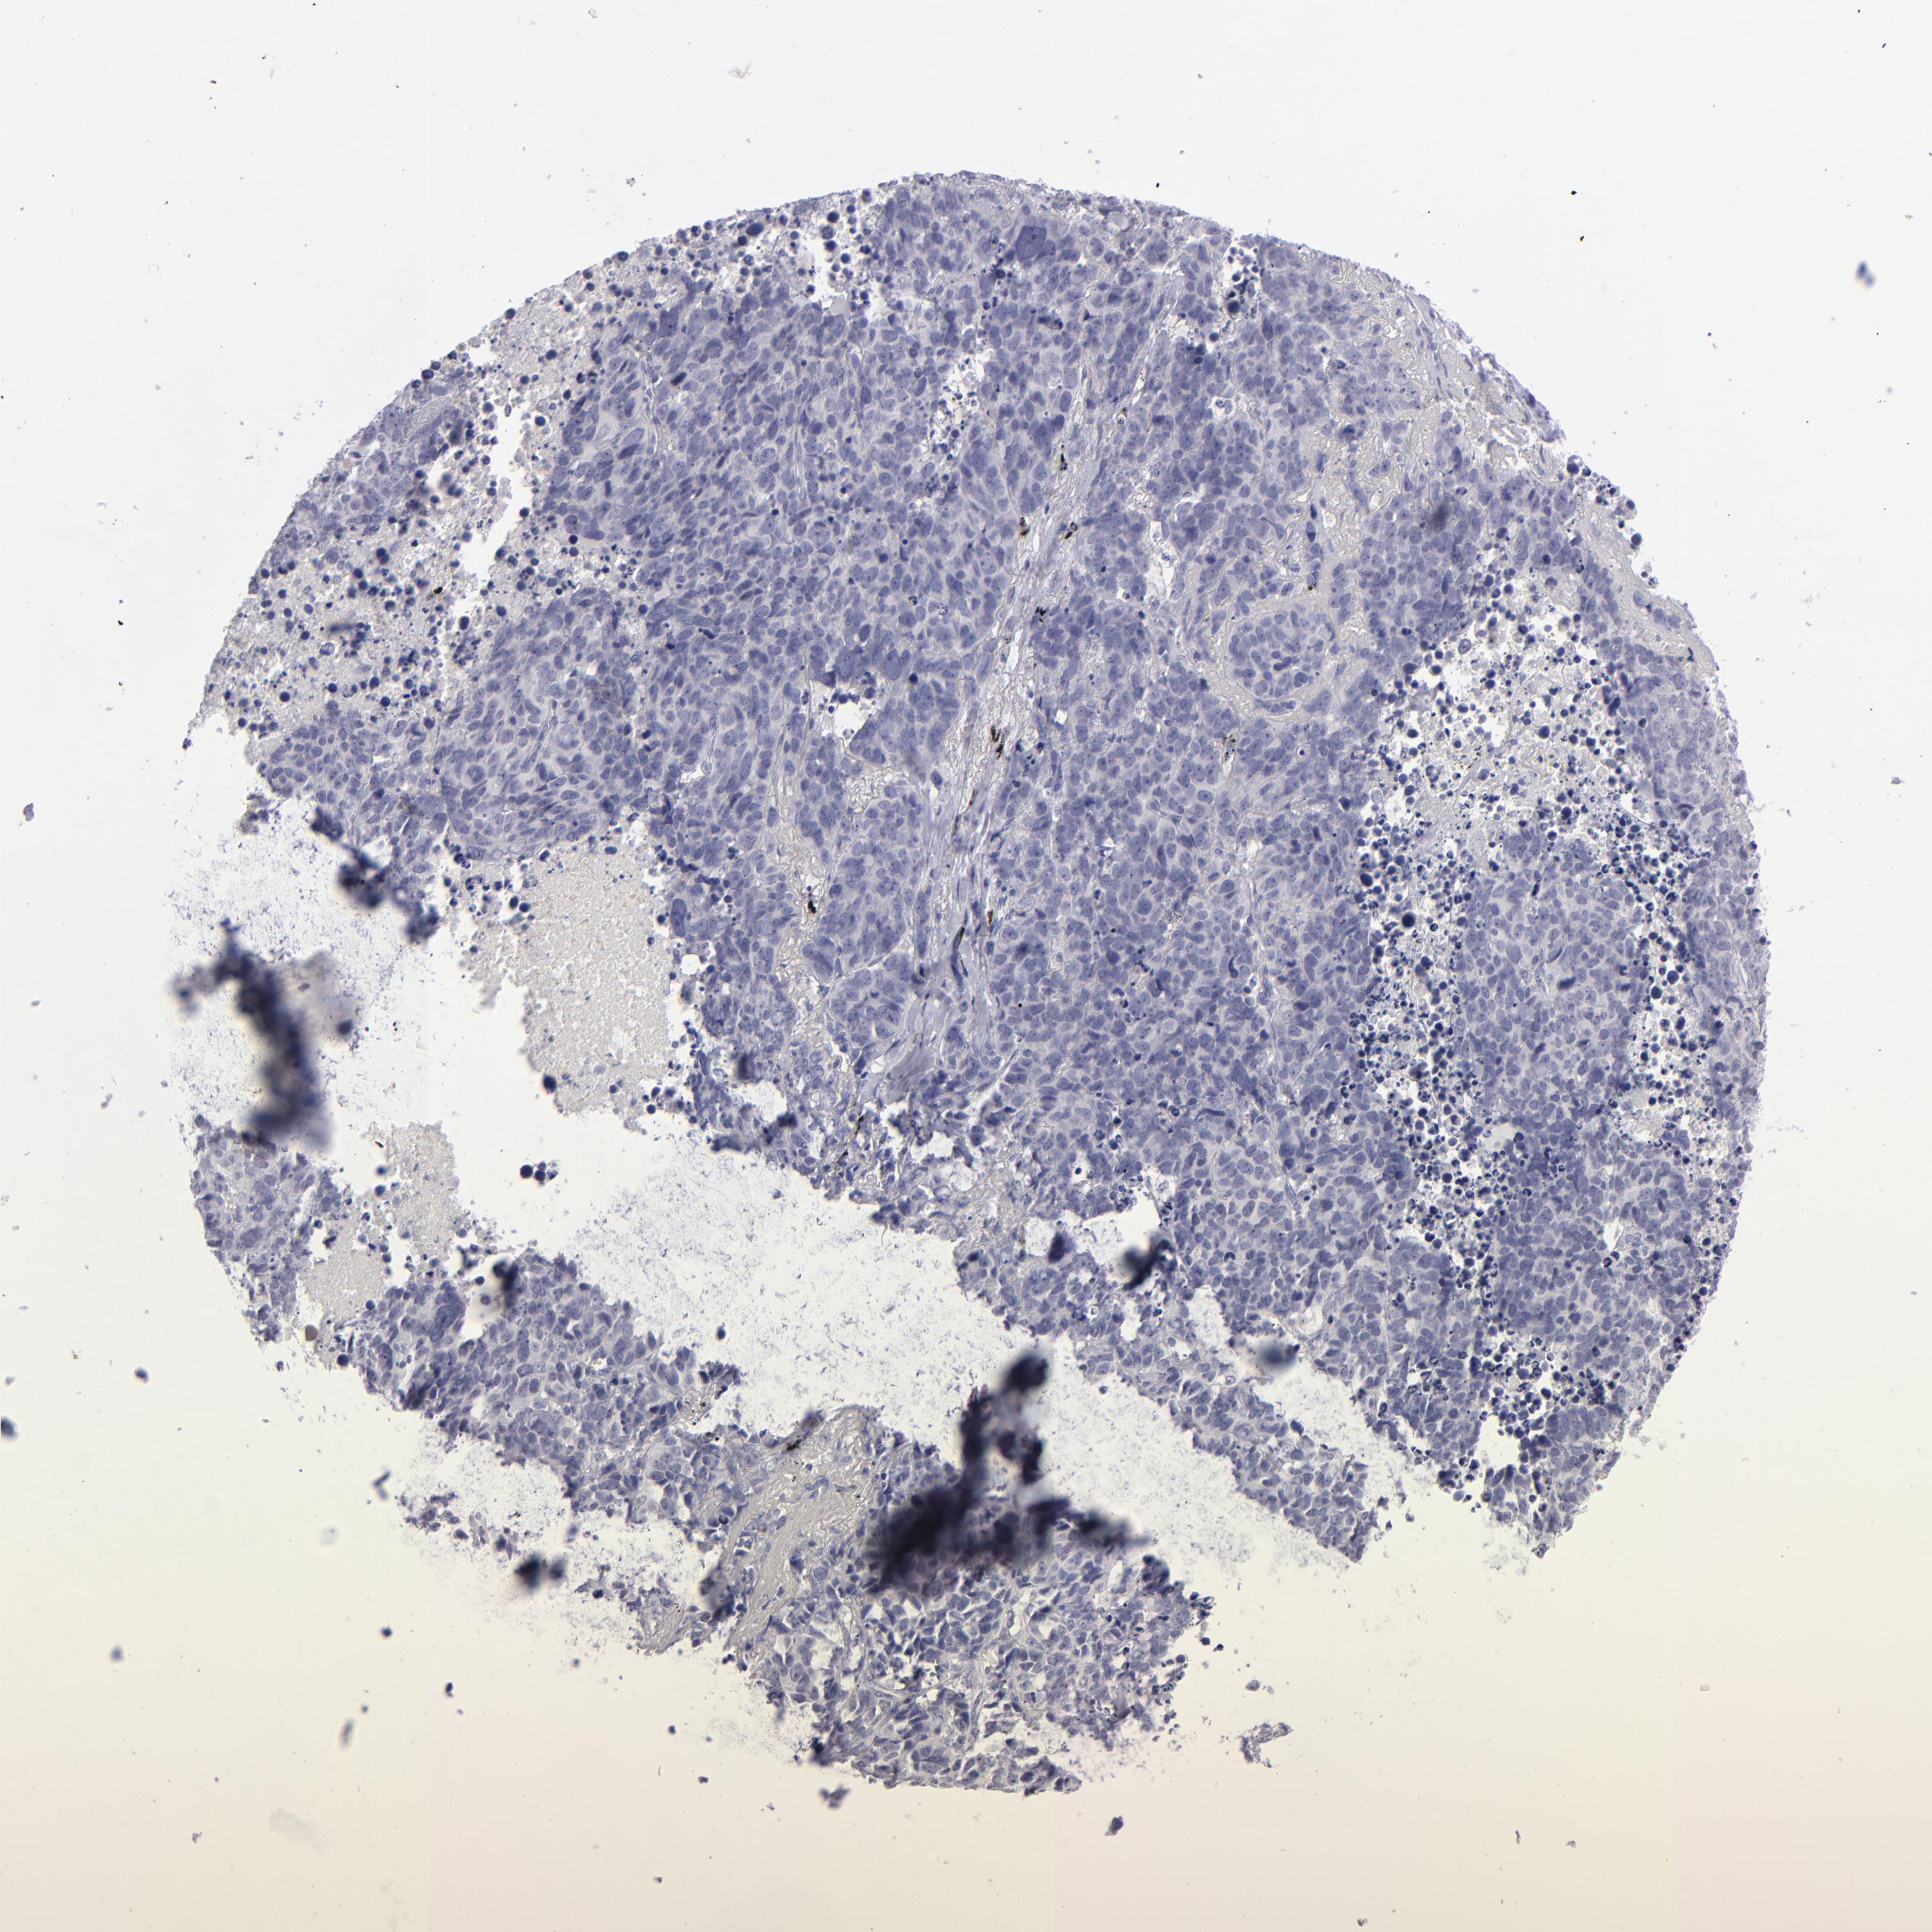

ITGB4 is not prognostic in Lung Squamous Cell Carcinoma (TCGA)

: 100.35